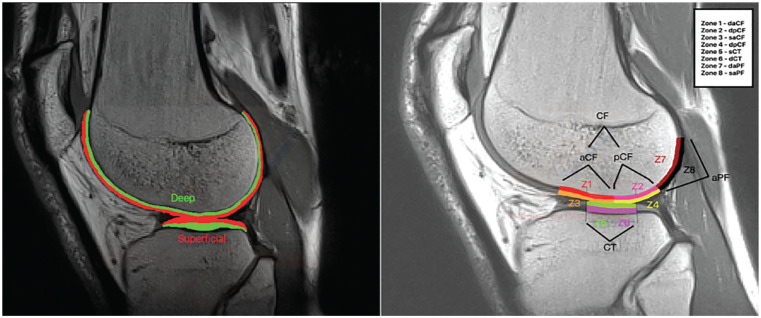

Methods: Knee forces and knee moments were obtained during walking trials of 20 healthy participants using statistical parametric mapping. The analysis focused on alterations across specific intervals of the stance phase, expressed as percentages of the gait cycle. T2RT values of cartilage were quantified using a 1.5 T magnetic resonance imaging at baseline and immediately after 45 minutes of walking in each condition.

Results: Significant differences were observed in knee force during the stance phase: (1) in the sagittal plane, greater values were between 2% and 9% and between 90% and 100%, and lower values were between 18% and 40% and between 62% and 85% in MF; (2) the frontal plane showed lower values between 7% and 14% and 98% in MF, and greater values were between 7% and 14% and 98% in MF; and (3) the transversal plane showed greater values between 0% and 9% and between 54% and 78%, and lower values were between 25% and 40% and between 81% and 100% in MF. Knee adduction moment showed significantly lower values between 0% and 8%, 32% and 90%, and >92% and 100%. Knee flexion moment showed significantly lower values between 3% and 5%, 25% and 69%, and >7% and 19% in MF. The main effect of loading in NF of cartilage showed significantly lower T2RT values in all superficial femur parts and significantly greater T2RT values in deep central tibia. MF showed significantly lower T2RT values in the superficial anterior-posterior femur in the medial cartilage compartment.

Conclusion: Increased knee moments in all planes reflect the effect of an acute change to particular footwear. NF reveals a greater response to loading in weightbearing knee cartilage zones. The superficial layers appeared to be more sensitive to loading after 45 minutes of walking.